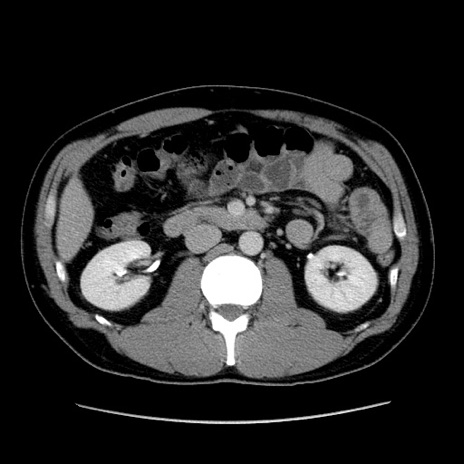

症例4(横断像)

【症例】30歳代男性

【主訴】腹痛、嘔吐

【現病歴】昨晩から突然の腹痛あり、その後嘔吐、軟便も出現。腹痛が改善しないため救急搬送となる。2日前にしめ鯖の食事歴あり。

【身体所見】意識清明、苦悶様、BP 135/90mmHg、BT 35.7℃、腹部:平坦、やや硬、心窩部〜臍部に自発痛、圧痛あり、筋性防御+、反跳痛-

【データ】WBC 8100、CRP 0.57